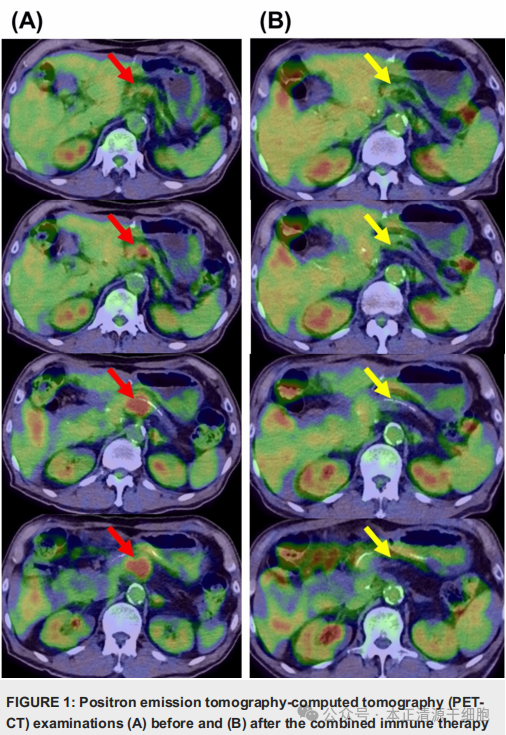

在连续约3个月,共7个周期的治疗后,医生们惊喜地发现:原本多处转移的肿瘤,在PET-CT影像检查中完全消失。肿瘤标志物CA19-9下降了38%,DU-PAN-2更是下降了72%。更令人鼓舞的是,患者不仅没有化疗常见的不良反应,体重与食欲反而逐渐恢复,整体健康状态显著提高。